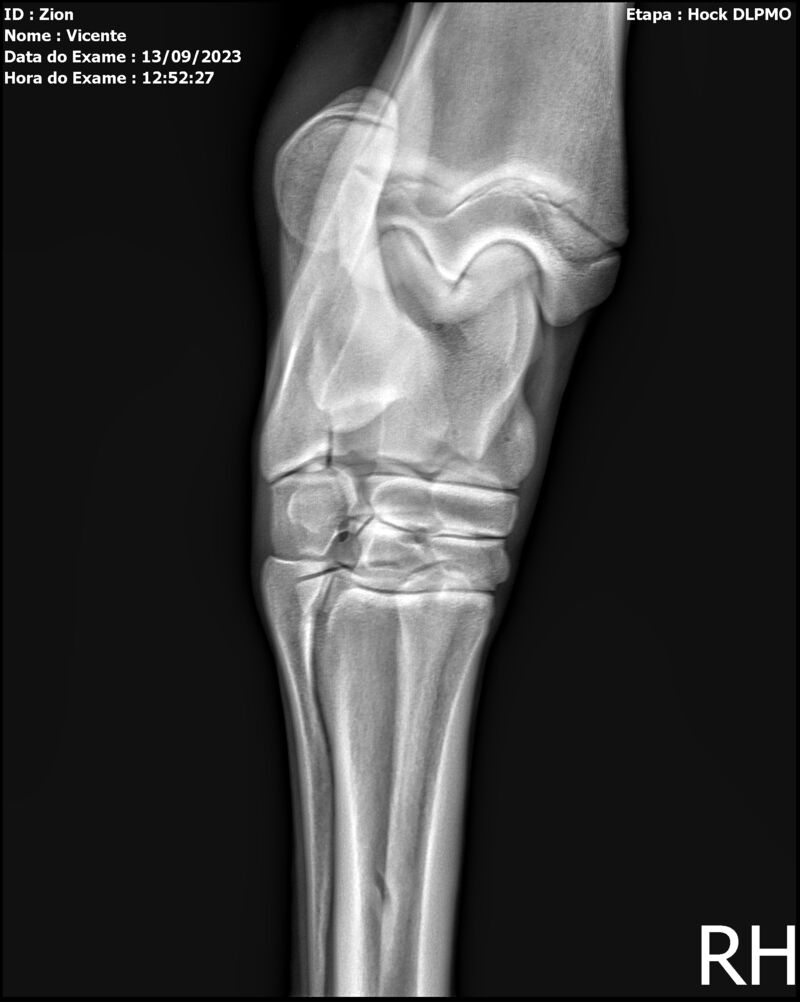

ZION ZC

Raça: BRASILEIRO DE HIPISMO

Sexo: MACHO - POTRO

Nascimento: 17/12/2022

Altura Aproximada: 1,51

Pel.: CASTANHO

Registro: EM AND

Vend.: VICENTE CONTE

Local : PORTO FELIZ/SP